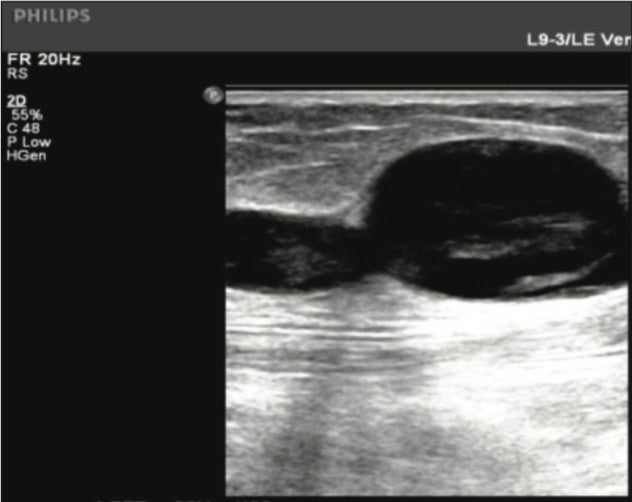

Figure 2. Thigh GSV Tributary one week post- Varithena treatment.

One week post-treatment: Venous duplex ultrasound of the lower extremity revealed a patent deep vein system and occluded GSV throughout the leg. The perforator vein in the calf was patent and compressible. The proximal extent of the thrombus in the GSV was approximately 2.5cm from the Saphenofemoral Junction (SFJ).